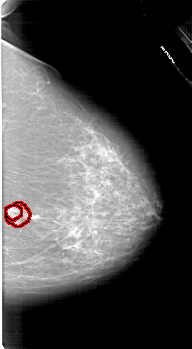

A_1618_1.LEFT_MLO

FILE: A_1618_1.RIGHT_MLO.OVERLAY

TOTAL_ABNORMALITIES 1

ABNORMALITY 1

LESION_TYPE MASS SHAPE IRREGULAR MARGINS SPICULATED

ASSESSMENT 5

SUBTLETY 3

PATHOLOGY MALIGNANT

TOTAL_OUTLINES 2